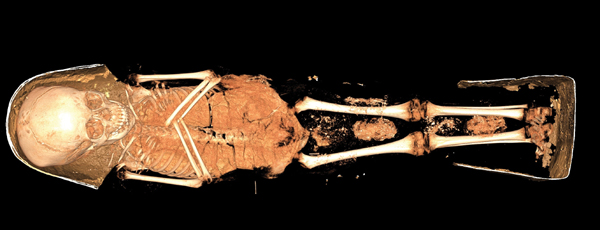

Let’s take, for example, the 2,000-year-old mummy of Sherit that resides at the Rosicrucian Egyptian Museum in San Jose. Sherit is the name given to the mummy of a girl of about four or five years old at the time of her death. Her body went through an intensive examination a few years ago and included the assistance of natural perfume maven Mandy Aftel in identifying and reconstructing the burial fragrance. Sherit lived during the Roman occupation of Egypt. A quick illness, perhaps dysentery, claimed the child suddenly. Judging from her funeral goods, Sherit came from a wealthy family, but child mortality was high even for the upper class at that time. Her mummification is quite classic for the period.

The organs were removed through an incision in the side of the abdomen. Her stomach, intestines, lungs and liver were placed in canopic jars and arranged between her legs. The brain was eviscerated via a small incision on the side of the cranium and then whisked with a reed before being drained through the nose. The cranium and body cavity was rinsed with palm wine as a type of disinfectant before the body was packed and covered with natron for dehydration. Sherit’s corpse would have remained in the salt for upwards of 40 days. Afterwards, the abdomen was packed with lichen, the heart was put back in the chest, and the skin would have been treated with a combination of aromatic gums, resins, pitch, bitumen and fragrant oils. Before her final wrapping and the application of her plaster cartonnage, the last ceremony was performed. This may have been done by her parents or perhaps the Master of Secrets (head embalmer). Frankincense and myrrh that had been steeped in Moringa oil was poured over the child’s body, inundating her with the scents of sanctity. Frankincense was a later addition to the arsenal of embalming and helped date the body. Analysis of the 2,000-year-old fragrance materials showed that both frankincense and myrrh came from modern-day Somalia. Which is still regarded as the greatest region for myrrh and frankincense cultivation in the world.